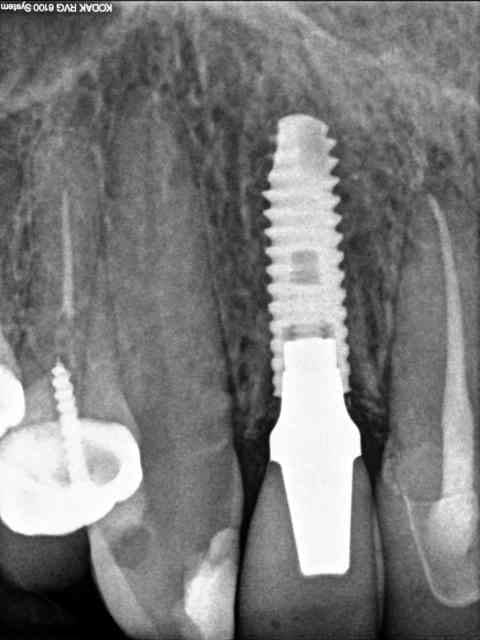

voici pour la radio de contrôle.